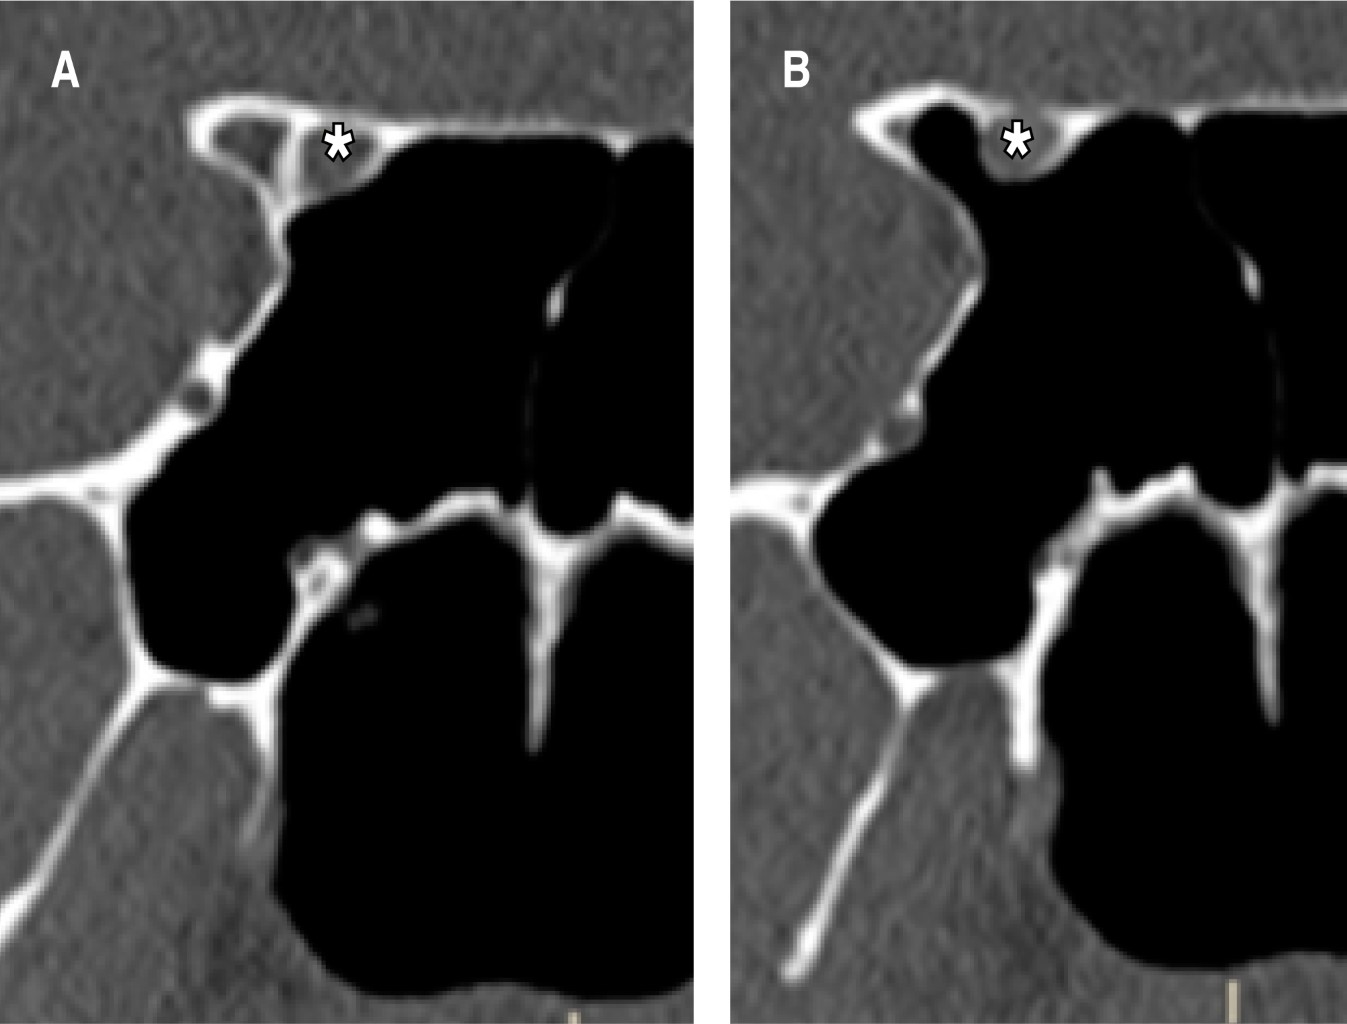

Basado en la extensión de la neumatización, el seno esfenoidal puede clasificarse en: tipo conchal, el seno esfenoidal es un espacio pequeño enfrente de la pared anterior de la silla turca. Tipo presellar, el seno esfenoidal se encuentra en relación a la pared anterior, la pared posterior del seno esfenoidal se localiza enfrente de la pared posterior de la silla turca. Tipo sellar, la pared posterior del seno esfenoidal está localizada entre la pared anterior y posterior de la silla turca. Tipo postsellar: la pared posterior del seno esfenoidal se localiza posterior a la pared de la silla turca (Figura 1).5,6

Según la clasificación de Delano, se puede hablar de cuatro variantes del trayecto del nervio óptico en cuanto a su relación con los senos paranasales. Tipo I, el nervio óptico cursa inmediatamente adyacente al seno esfenoidal pero sin tener contacto con las celdillas etmoidales posteriores, ni indentar la pared. Tipo II, cursa adyacente al seno esfenoidal causando la indentación de la pared del seno. Tipo III, atraviesa el seno esfenoidal y es rodeado en al menos 50% por aire. Tipo IV, está en contacto directo con el seno esfenoidal y con las celdillas etmoidales posteriores (Figura 2).1

Figura 1

Figura 2